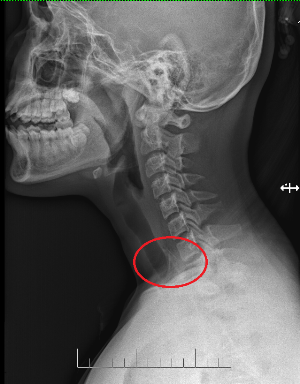

Theo người nhà cho biết, trước đó do thói quen vừa ăn uống vừa xem tivi, bé gái đã bất cẩn nuốt phải dị vật lớn. Sau khi nhập viện do xuất hiện các tình trạng nuốt vướng, đau nhiều vùng hạ họng, các BS đã tiến hành thăm khám, chụp X-Quang vùng thực quản nghi ngờ có dị vật tại thực quản đoạn ngang đốt sống cổ C2. Ngay sau đó, các BS đã hội chẩn và thực hiện nội soi thực quản an thần để gắp dị vật ca ngoài.

Sau 60 phút, dị vật được gắp thành công là một mảnh xương đùi gà dài 2,5cm, rộng 1cm với nhiều cạnh sắc nhọn, nham nhở. Bệnh nhân được xuất viện ngay trong ngày.